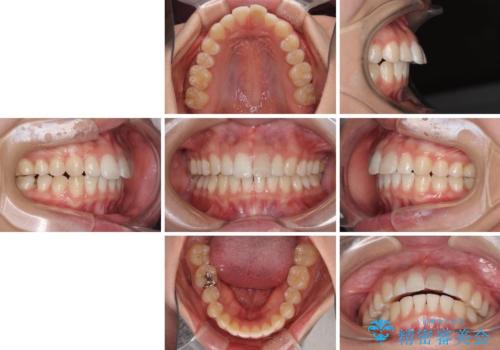

気になる前歯を治したい インビザライン矯正とオールセラミッククラウン

- 変色した前歯と突出した口元を気にして来院された患者様です。

口元の突出感はインビザラインにより歯列を整え、その後に、前歯をオーダーメイドタイプのオールセラミッククラウンにて補綴治療することとしました。

長時間のマウスピース装着と、患者様自身でのゴムかけに協力いただき、口元の突出感をしっかりと改善することができました。

前歯のオールセラミッククラウンもまるで本物の歯のように仕上がり、患者様には大変満足していただきました。